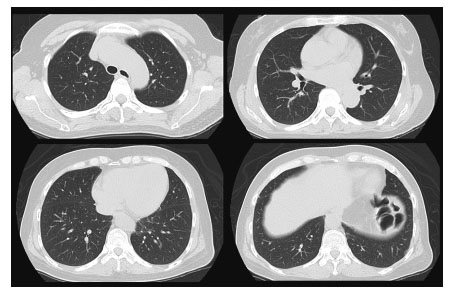

Time course of chest CT images.

(a,d) Pneumomediastinum, consolidation and patchy GGO were shown in both lungs. (b,e) Pneumomediastinum was disappeared 2 months after immunosuppressive treatment. GGO and consolidation were still showed bilateral lobes.

(c,f) CT showed lung fibrosis mainly in the left lobe, but consolidation and GGO dramatically improved 1 year after immunosuppressive treatment.

Noninvasive positive pressure ventilation was started. We selected combination therapy, including high-dose mPSL 1 g pulse for 3 days, followed by 80 mg/day of PSL and intravenous cyclophosphamide (IV-CY; 500 mg/m2). Six days after IV-CY therapy, leukocytopenia occurred (WBC 1,800/μL, Ly 54/μL) and the patient was treated with granulocyte-colony stimulating factor. With these treatments, the creatine kinase and myoglobin levels were decreased after the 14th day. On the other hand, pneumomediastinum was further complicated with RP-ILD (Figure 5 a, d) and her respiratory failure progressed and oral intubation with mechanical ventilation was introduced on the 8th day of hospitalization.

Mediastinal emphysema disappeared but new ground-glass opacity appeared on CT at day 60 (Figure 5 b, e). We started tacrolimus on 80th day which was increased finally up to 4 mg, while PSL was tapered. Following 2 months of therapeutic courses, the patient gradually improved, oxygen requirement decreased and she was withdrawn from artificial ventilation. Six months later, the anti-MDA5 antibody titer had decreased to 75 Index. The serum ferritin level increased to a maximum value of 975 ng/mL on day 16, which also declined in line with clinical improvement. The patient was transferred to another hospital for rehabilitation (Figure 5 c, f). Ultimately, she returned home with domiciliary oxygen therapy (1 L/min) and remains under treatment as an outpatient at our hospital (Figure 6).